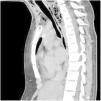

This is the case of a 17-year-old girl with a past medical history of childhood meningoencephalitis without sequelae, with a 1-week history of neck pain, odynophagia, and fever of up to 39 °C. On physical examination, vital signs were stable, and she exhibited cervical pain upon movement. The lab test results showed elevated acute-phase reactants. The cervical and thoracic CT scans performed revealed the presence of a large cervical collection with abundant gas bubbles inside (asterisks) spreading toward the posterior mediastinum through the retropharyngeal space, which were findings consistent with necrotizing fasciitis and posterior mediastinitis. Surgical samples cultured Streptococcus dysgalactiae and S. intermedius. The patient responded favorably to antibiotic therapy and surgical drainage of the collection (Figs. 1, 2 and 3).